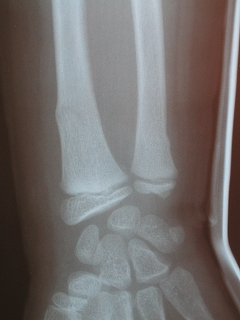

‰E‘O˜rœœÜ

@@”N—î@@8Î@—«

@@•‰“ú@•½¬14”N7ŒŽ27“ú

œÜÇ—á